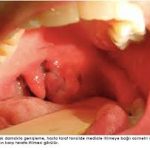

Tonsil muayenesi Kızarıklık, bademcik büyümesi, bazen beyaz püskürme Tonsil itilir, peritonsiller bölgede şişlik ve yanak/yan duvarda çıkıntı

Asimetri Genellikle simetrik Tonsiller arasında asimetri (etkilenen tarafta daha belirgin)

Ağız içi asimetri, uvula deviasyonu

B) Cerrahi / Girişimsel Tedavi

Peritonsiller apse kesinlikle çoğu zaman boşaltılmalıdır:

1. İğne aspirasyonu (needle aspiration)

2. İnsizyon ve drenaj

• Ağız içinde bir taraf şişmiş/itilmiş görünür

• Uvula (dil ucunun arkası) karşı tarafa deviye olabilir